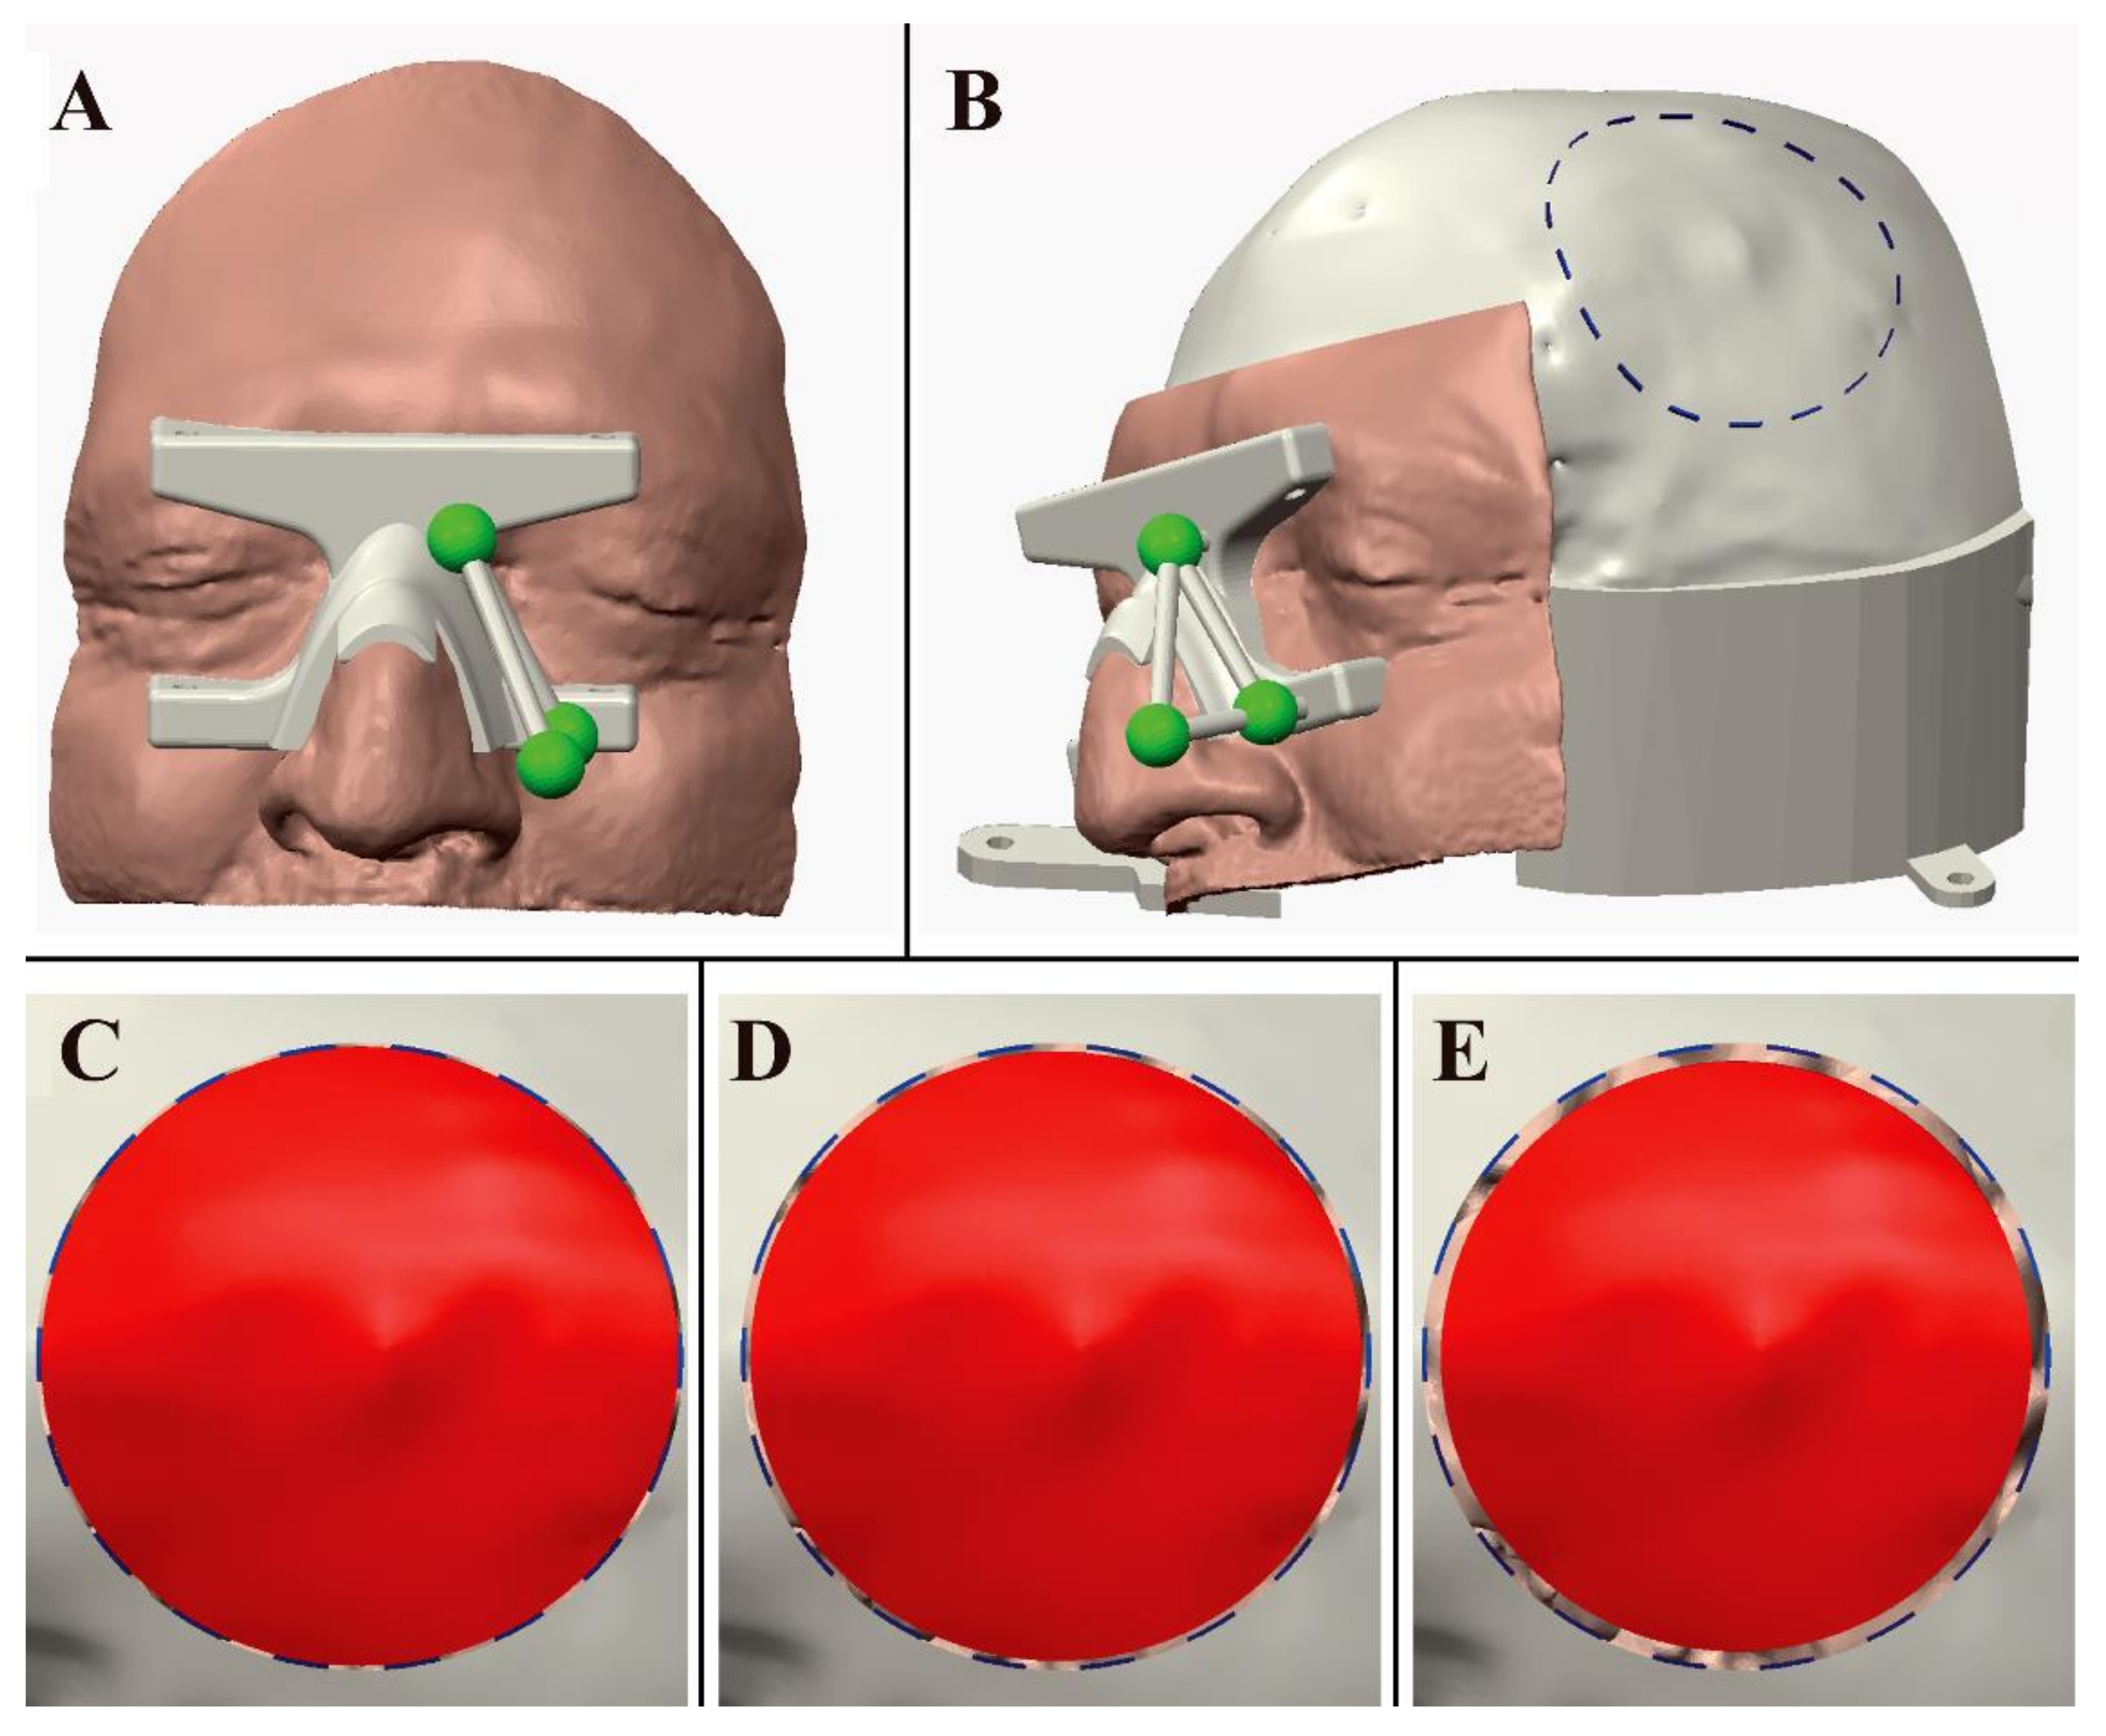

2.2. VOSTARS HMD-Based Surgical Navigation Platform and Template-Based Registration

2.3. AR Visualization Modalities